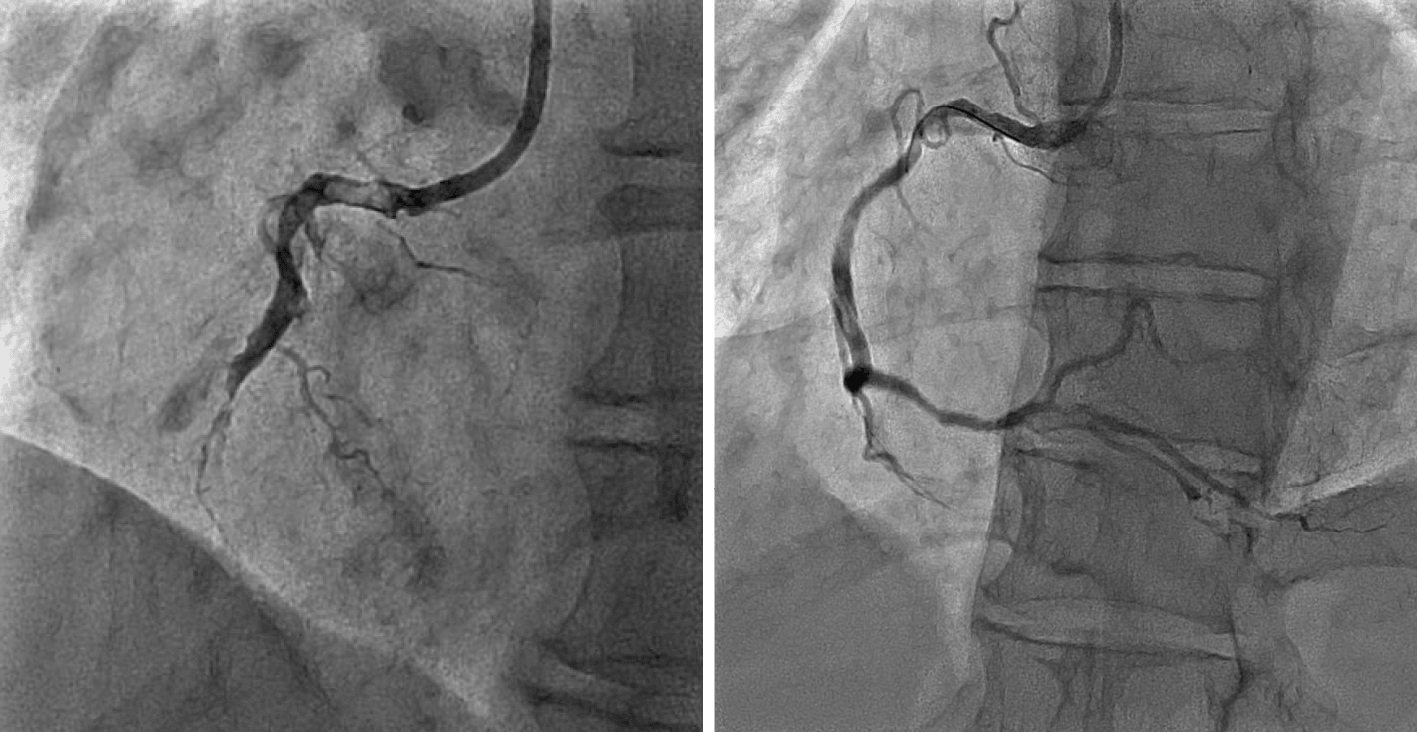

Coronary Angioplasty

In the 1980s, coronary angioplasty could only be undertaken if cardiac surgery was available on site as a backup. Coronary angioplasty was part of the plan for cardiac surgery at Waikato – the plan being to allow cardiac surgery to bed-in before starting coronary angioplasty. The first coronary angioplasty at Waikato Hospital was undertaken in April 1990, 13 months after the commencement of cardiac surgery.

Cardiology continued to evolve, and immediate angioplasty (“primary angioplasty”) for certain types of heart attack became the standard of care. Patients are shipped from the ED to the Cardiac Laboratory within an hour of arriving at Waikato Hospital and a stent is implanted into the relevant blood vessel.

Over 20,000 coronary angioplasties (including 2000 primary angioplasties) have been performed at Waikato Hospital.